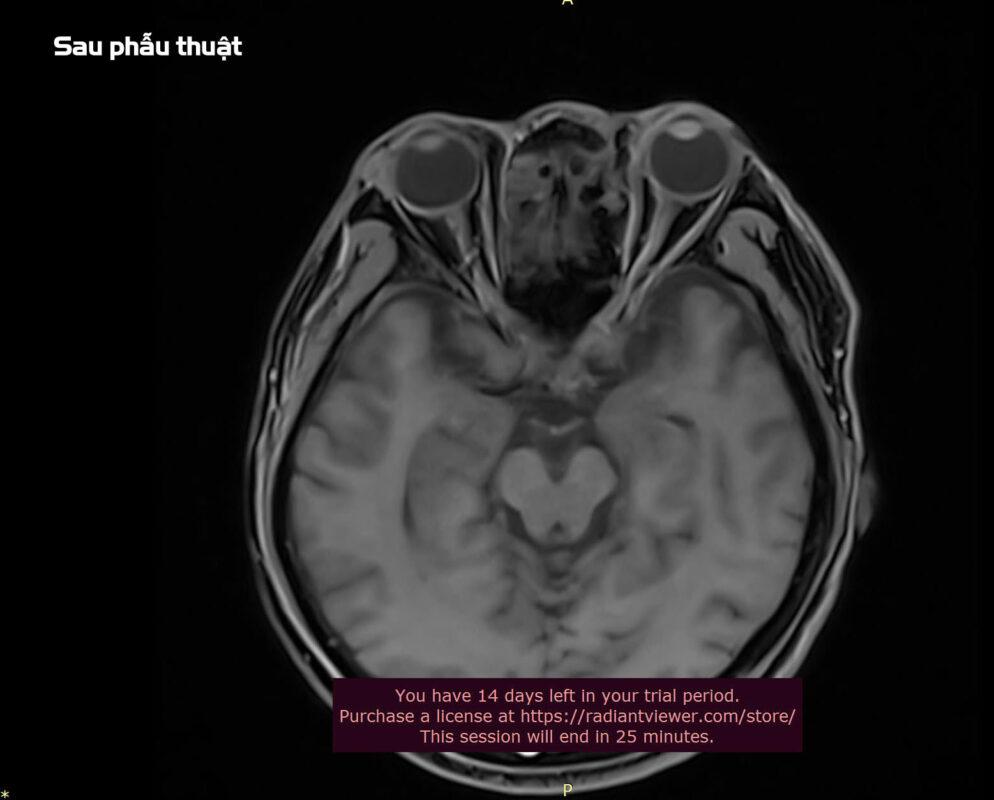

Sau 5 ngày điều trị tích cực với kháng sinh, kháng viêm và chăm sóc hố mổ, bệnh nhân đã hồi phục nhanh chóng, các triệu chứng song thị biến mất, cử động nhãn cầu trở lại bình thường và được xuất viện.